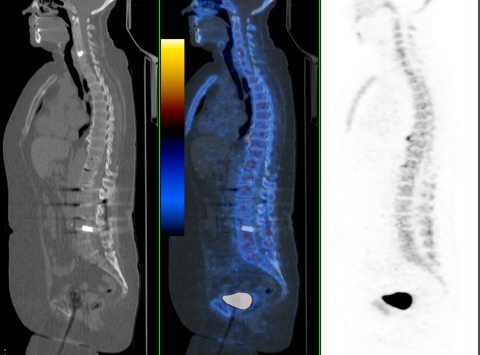

Fig. 6.

59-year-old female patient 91 and 106 months postoperatively with no increased uptake either around her cervical (C5/6) or lumbar cage (L3/4) (patient no 19). Sagittal low-dose CT, fused PET/CT, PET

Regarding lumbar intercorporal fusions, there were two patients with two intercorporal fusions showing either both no increased uptake or one an increased uptake (Figs. 4, 5). Three patients had received both cervical and lumbar intercorporal fusions only one of them showing no increased uptake in both regions (Fig. 6).